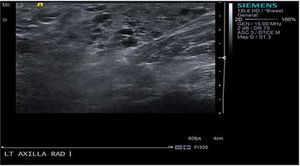

Case History: 29-year-old female, five days postpartum, presented with painful swelling and palpable lump.